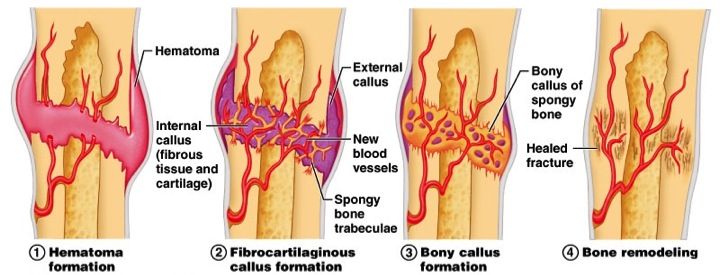

Sometimes dental implants can become infected and cause inflammation of the soft tissue and bone loss around the implant, often of a condition called Peri-Implantitis. Peri-implantitis is an inflammation similar to gum disease, and it affects the gum tissue and the supporting bone around a dental implant.

What happens if a tooth implant gets infected?

When the infection attacks the bone, the bone begins to deteriorate. Thus, the implant loses its support and may begin to feel loose. In severe cases, the infection can sneak into the bloodstream and cause systemic health problems. Surgery is usually necessary to treat peri-implantitis.

Peri-implantitis – This is what gum disease is called when it affects a dental implant. If you do not take care of the gums properly, the implant area can become infected and the surrounding bone and gums will be damaged by bacteria. This can cause the implant to loosen.

What is the most common cause of implant failure?

Gum infection around the implant The most common reason for dental implants to fail is due to an infection in the jawbone around dental implants, called peri-implantitis. Although implants cannot develop tooth decay, they are still susceptible to the implant form of gum disease.

Why did my dental implant fail? The most common cause of failure of the dental implant is failed osseointegration, or when an implant does not adhere properly to the jawbone. Infection, tissue damage around the implant, sinus problems or allergic reactions and rejection can also cause implants to fail.

What is the most common cause of implant failure? Dental implants can fail for a number of reasons, but the most common – and most preventable – are infection and bone loss. Peri-implantitis is a type of infection that forms around the implant and inside the gums.

Can dental implants loosen over time?

Bone loss can also be the cause of a loose dental implant. If you have had some damage to the bone density over time due to infection, gum disease or lack of successful bone integration, the implant screw may come loose. These cases are more severe and will require emergency treatment to remove the implant screw.